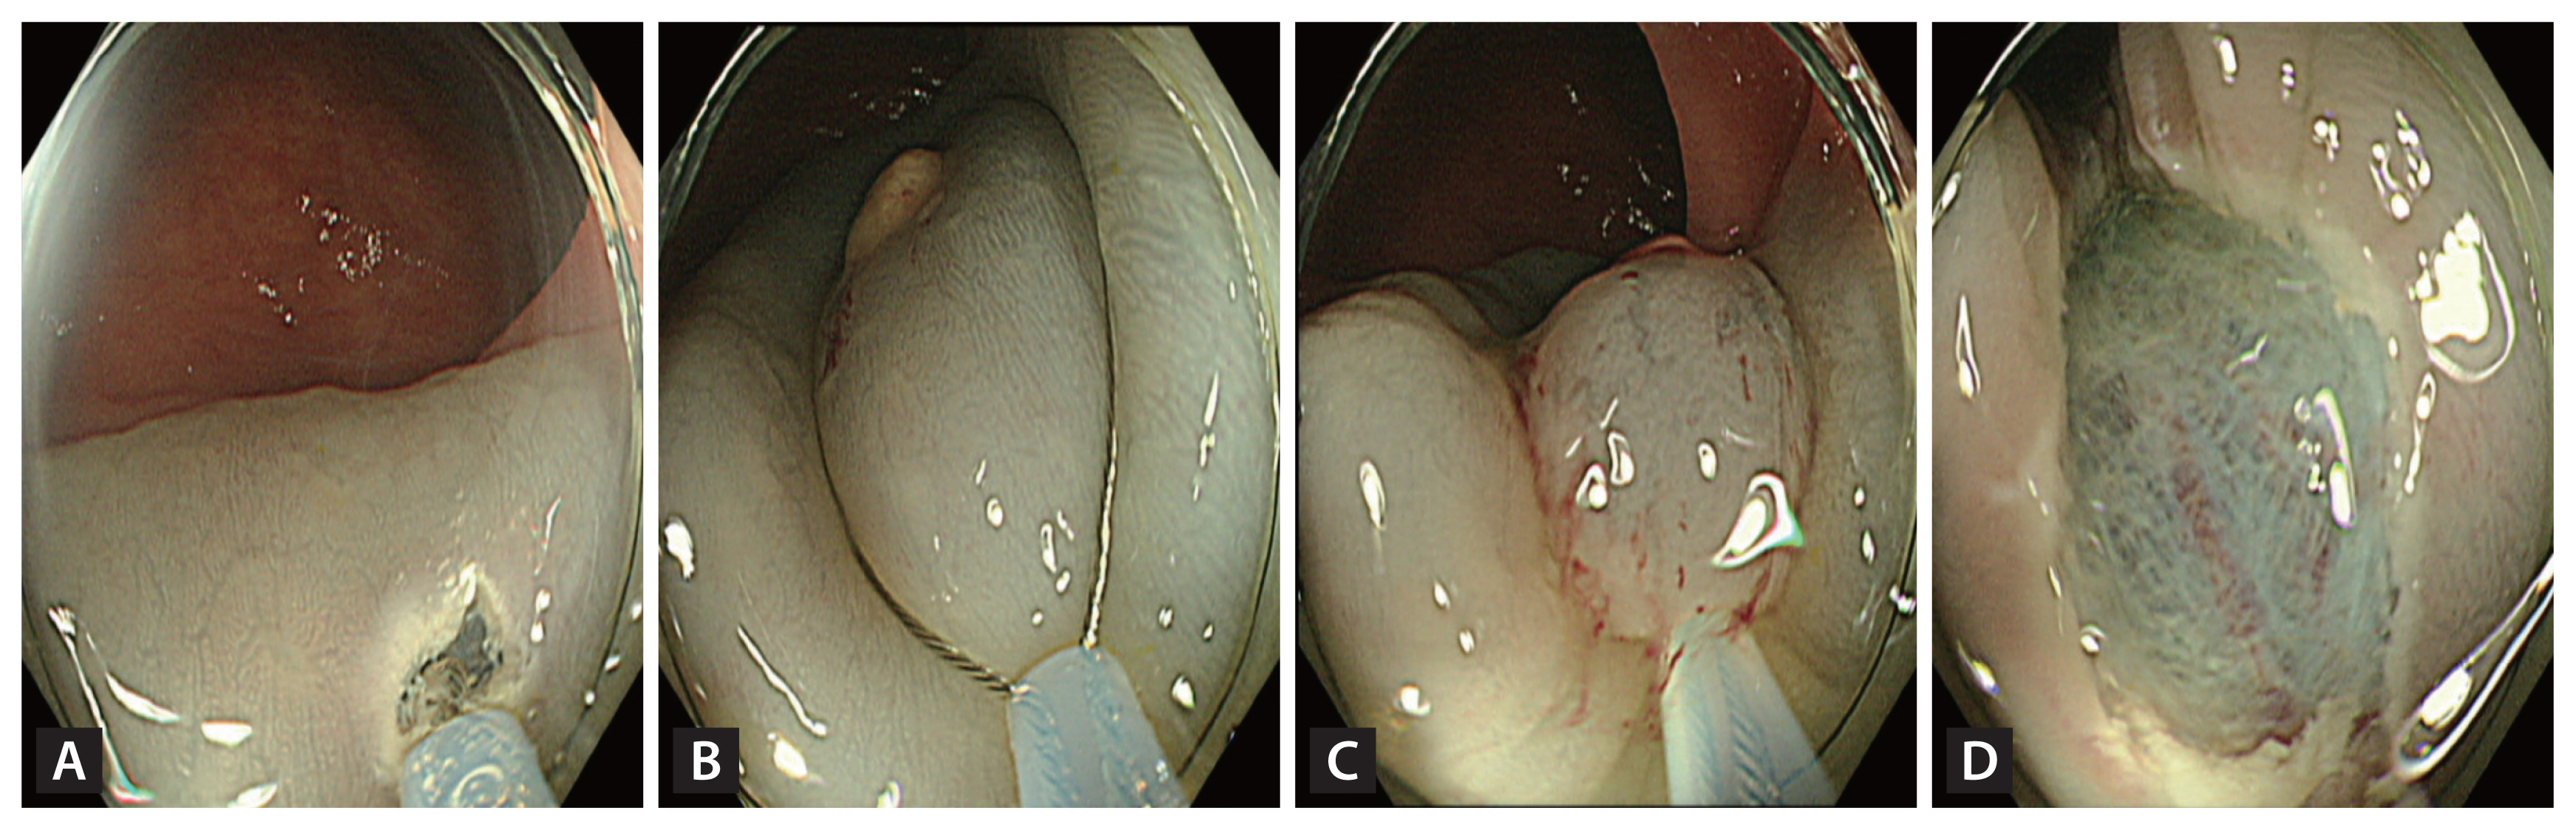

A high-definition colonoscope (CF-HQ 290 EVIS LUCERA ELITE; Olympus Corporation, Tokyo, Japan) with a transparent cap and 13-mm oval type stiff snare with a 0.42-mm wire diameter (Captivator; Boston Scientific, Marlborough, MA, USA) were used for both the methods. The EMR-P procedure was performed as follows: a mixture of normal saline, 1:100,000 epinephrine and indigo carmine were injected submucosally to lift the lesion. Using the tip of the snare, a fully circumferential incision was made around the lesion. Next, the lesion was snared along the circumferential incision and resected with an electric current (Fig. 1). For the Tip-in EMR procedures, the same submucosal solution was injected around the lesion, and a mucosal slit of 2–5 mm in width was made approximately 5 mm from the proximal edge of the lesion [27]. Next, the tip of the snare was anchored into the mucosal incision, and the snare was slowly opened. Furthermore, the snare was gently pressed towards the anchor site to maintain the width of the snare and ensure a leverage effect for the lesion [27]. The snare sheath was pressed downward to entrap the deep submucosal tissue together with the lesion [27]. Finally, the captured lesion was resected using the electric current (Fig. 2).

Images of precut endoscopic mucosal resection. (A) Inject submucosal solution around the lesion. (B) Use the snare tip to precut circumferentially around the lesion with an adequate margin. (C) Capture the lesion including the margin using the snare. (D) Image after resection.